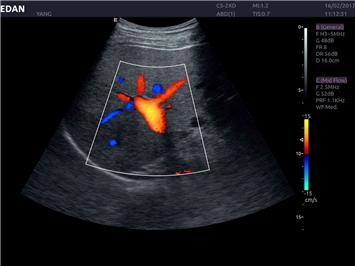

EDAN Acclarix LX4

Расширьте свои представления. Использование усовершенствованной платформой Acclarix система LX4 обеспечивает непревзойденную четкость изображений и интеллектуальный рабочий процесс для всех пользователей, являясь при этом наиболее экономичным решением.

EDAN Acclarix LX4 представляет собой инновационную ультразвуковую систему, построенную на усовершенствованной платформе Acclarix. Сочетание высокого качества визуализации с интеллектуальным рабочим процессом делает эту систему оптимальным выбором для клиник, ценящих эффективность и экономичность.

• Кардиологических исследований

Трехмерная реконструкция ЦДК:

Да

Color 3D: